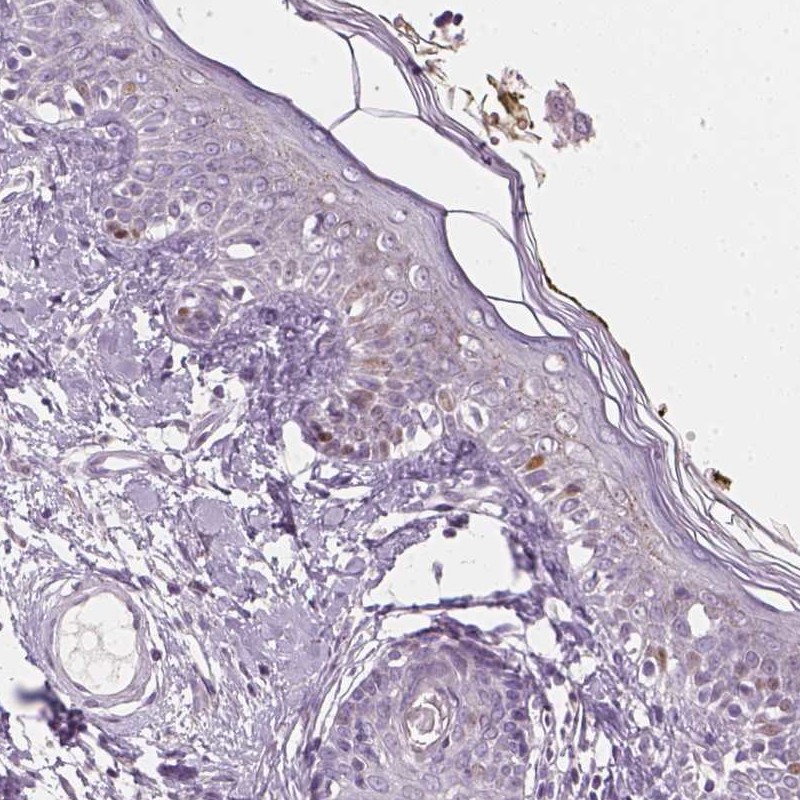

Enhanced - Orthogonal

Antibody staining mainly consistent with RNA expression data across 44 tissues.

HIGH EXPRESSION

Skin 1

RNA expression: 36.4 nTPM

LOW EXPRESSION

Cerebellum

RNA expression: 2.4 nTPM